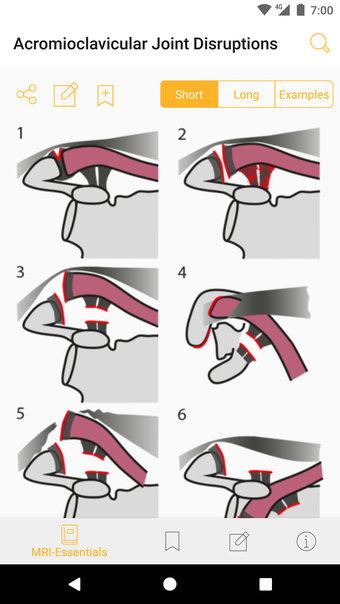

Jedes Thema wird in wenigen Seiten behandelt. Es gibt kurze Absätze mit einfachen Zeichnungen.

Die Pro-Version enthält mehr als 4.000 hochwertige Bilder von herausragender Bildqualität, die den Text veranschaulichen. Sie sind so konzipiert, dass sie dem Leser einen schnellen Überblick über die wichtigsten Informationen zum Zustand geben.